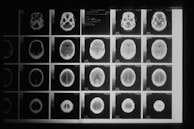

CT Scan

A CT scan, or a Computed Tomography scan, is a cutting-edge medical imaging technique offered at Dr. Thorat's Pathology Laboratory. This advanced technology allows for detailed cross-sectional imaging of the body, providing valuable insights into various medical conditions.